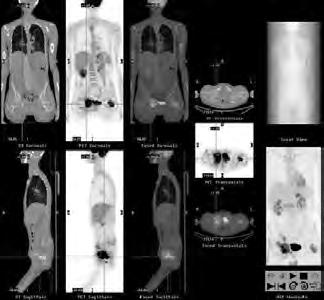

2.6.4 Radionuklidové metody (Daniela Chroustová) 35